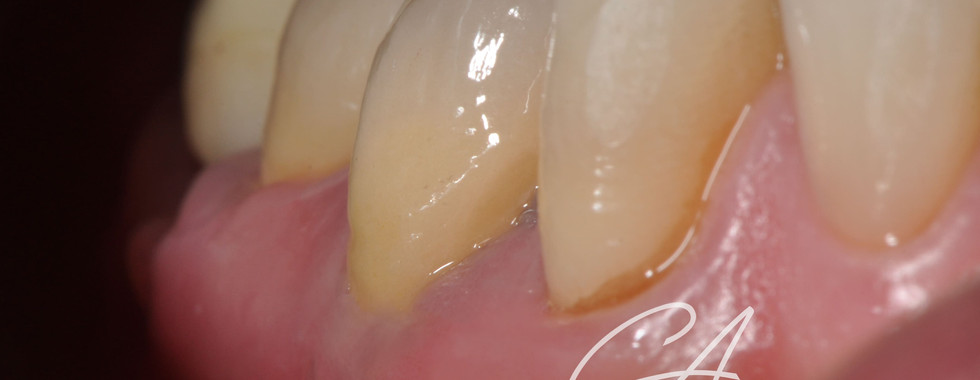

Buongiorno a tutti, oggi mi piacerebbe condividere con voi un caso multidisciplinare. Il paziente si presenta per ricorrenti ascessi in sede 45 e 44. Entrambi gli elementi vengono sagomati con strumenti espansivi. L'elemento 44 viene otturato con tecnica single cone e bioceramico mentre l'elemento 45, a causa del diametro importante (> 80) e per la forma ovale del sistema endodontico, viene sottoposto ad apical plug in MTA. Gli elementi vengono poi sottoposti a fase ricostruttiva (in seguito a disassembling delle corone) e limati con tecnica BOPT e il provvisorio viene mantenuto diversi mesi per condizionare i tessuti. Tutto bene, fino a quando non mi sono fatto realizzare le corone definitive. Ho notato subito che avrei ottenuto una vistosa disomogeneità dei livelli gengivali; ho pertanto deciso di proporre al paziente (a mie spese), un innesto gengivale libero per l'ispessimento dei tessuti gengivali. Ho quindi modificato la lunghezza e il profilo di emergenza della corona 44 e cementate entrambre le corone con cemento provvisorio in attesa della maturazione dei tessuti.

Il controllo dei tessuti gengivali è ancora precoce ma la guarigione radiografica periapicale è a 1 anno (ultima radiografia visibile).